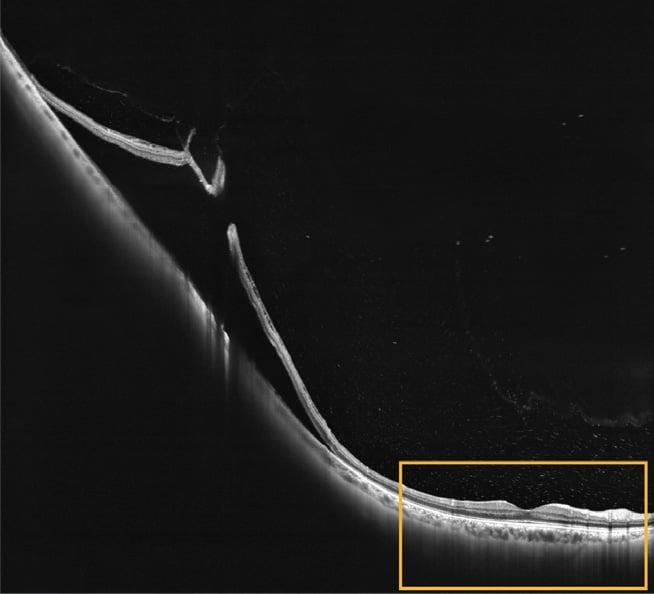

Intalight’s Dream optical coherence tomography (OCT) is the next generation ultra widefield swept source OCT that transforms the way we diagnose and manage.

Deep: SuperDepth OCT imaging up to 12 mm of the retina and 16.2 mm into the anterior segment.

Rapid: A-scan rate of up to 400,000 Hz to significantly improve workflow.

Extensive: Ultrawide single-capture (130°) combined with montage to expand coverage beyond 200°.

Accurate: True angio algorithm features artificial intelligence-driven analysis including automated layer segmentation.

Multimodal: OCT, OCT-angiography, anterior segment analysis, and biometry with one device.

Contact: OphthalmoPro (AUS) 1300 578 288